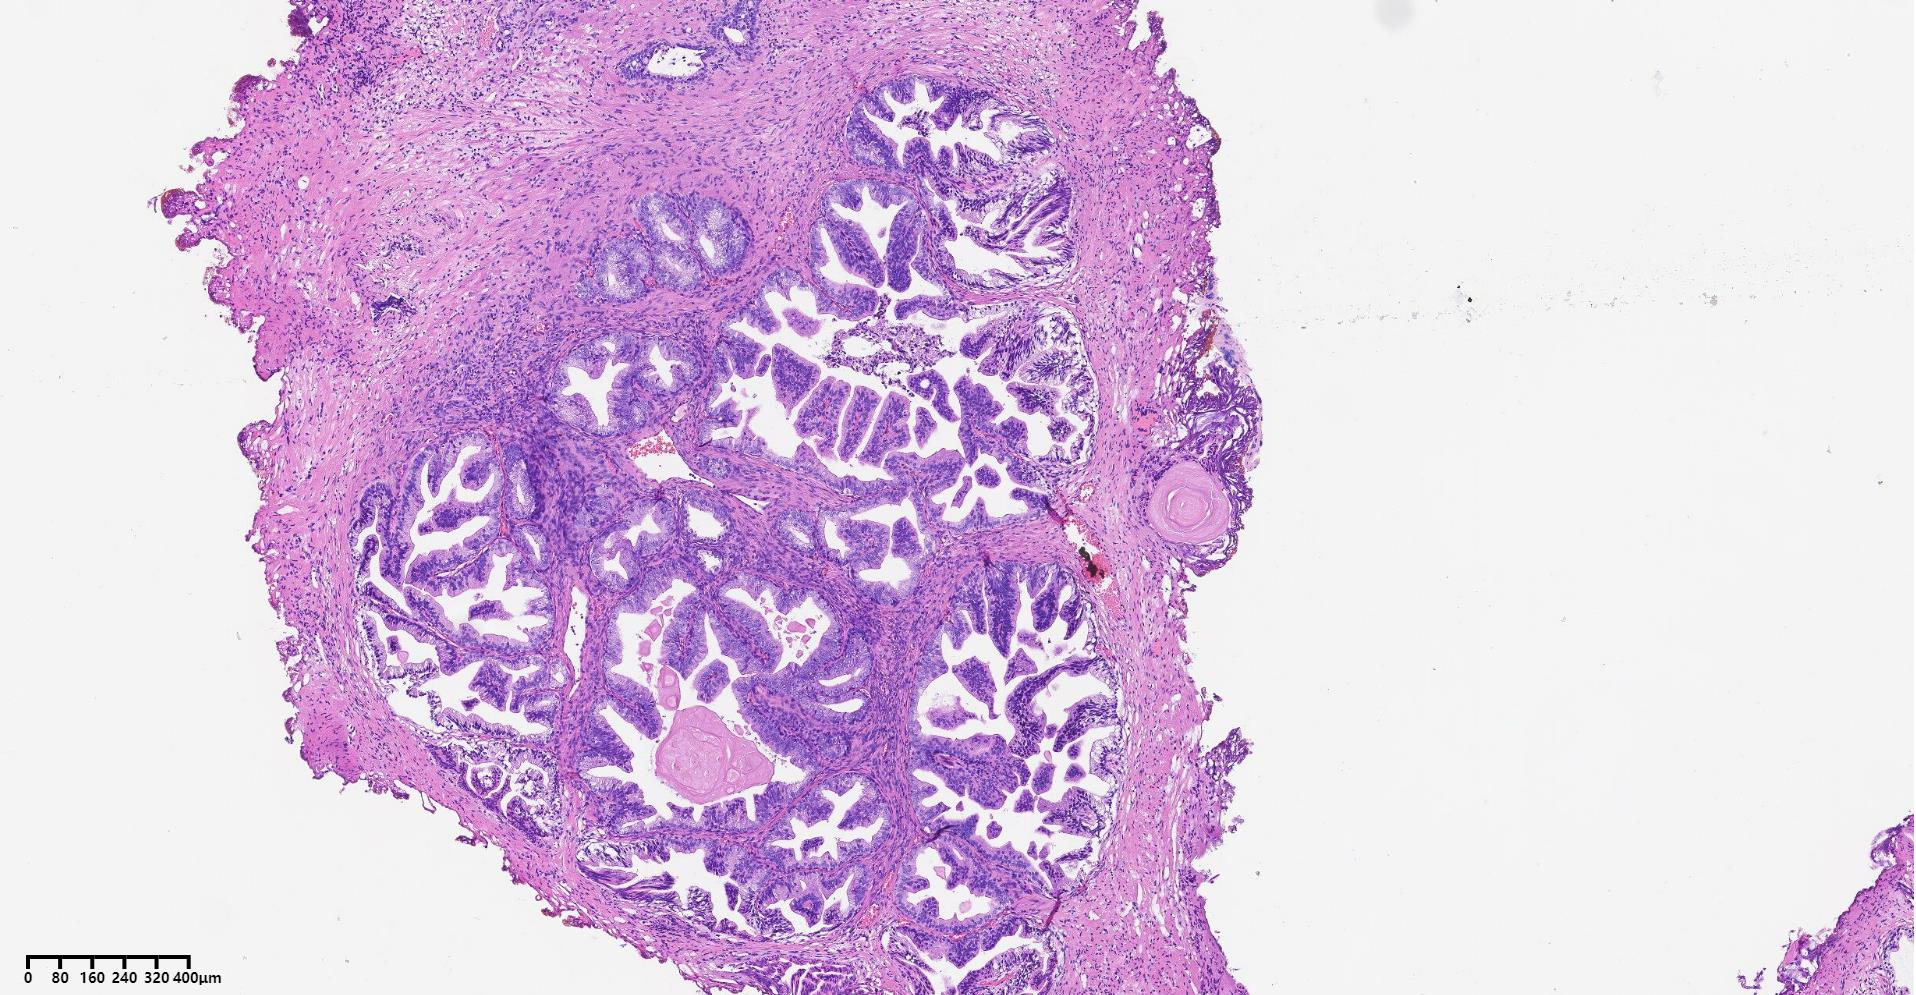

前列腺PIN?

发现肉眼血尿5月余,PAS 5.7

标本名称

经尿道前列腺等离子电切组织

大体所见

碎软组织一堆,共直径5.2

BPH.

嗜酸性大核仁,胞浆透亮,PIN没问题。还是组化一下吧,